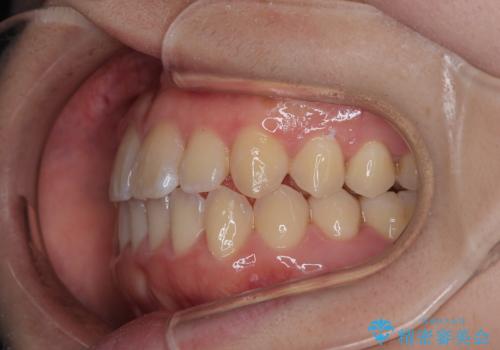

【インビザライン】前歯のがたつきを目立たない装置で治療

- 前歯の叢生を主訴に来院されました。目立たない装置を希望されたためインビザラインで治療を行いました。

IPRと拡大をし、叢生を治しました。右上2番は反対咬合でしたが短期間できれいに治りました。